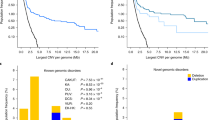

The deletion was confirmed by quantitative real time-PCR and SNP genotyping via traditional Sanger sequencing in the index case and the unaffected parents. The CNV was absent in both parents, indicating a de novo event. Additional genotyping of highly informative SNPs (heterozygosity approx. 0.5) in the region confirmed that the index case carried a maternal haplotype in homozygosity, thereby also confirming that the deletion occurred de novo in the paternal chromosome. We next performed comprehensive annotation of this region using public databases, including the National Center for Biotechnolgy Information (NCBI) Genome Browser (URL: http://www.ncbi.nlm.nih.gov/), Genome Reviews (URL: http://www.ebi.ac.uk/GenomeReviews/), Online Mendelian Inheritance in Man (OMIM; URL: http://www.omim.org/) and PubMed (www.ncbi.nlm.nih.gov/pubmed/). According to the NCBI Genome Browser (build 37.2), the region of the 3q13.31-22.1 deletion contains 101 known genes (Fig. 3). We cross-referenced these transcripts against the OMIM database and identified 23 annotated genes previously associated with a disease phenotype in humans (Table 1). Using the probabilistic model that integrates genomic, evolutionary, functional and network properties of haploinsufficient genes [15], we predicted that the deletion is highly deleterious with a haploinsufficiency LOD score of 49.2. We next compared the deleted region against the ECARUCA (European Cytogeneticists Association Register of Unbalanced Chromosomal Aberrations; URL: http://umcecaruca01.extern.umcn.nl:8080/ecaruca/ecaruca.jsp) and DECIPHER (URL: http://decipher.sanger.ac.uk/) databases of rare cytogenetic abnormalities. All previously reported deletions overlapping with the 3q13.31-22.1 region are summarized in Table 2. For each of the observed phenotypes in our case, we performed detailed analysis of candidate genes. Moreover, considering the frequent occurrence of CAKUT and ACC among these cases, we performed detailed mapping of partially overlapping deletions in patients with these phenotypes (Fig. 4). The analysis was performed under the assumption of incomplete penetrance, thus only the cases with reported CAKUT or ACC phenotypes were included in the mapping.

The reported deletions in all cases with agenesis of corpus callosum (ACC, middle panel) and congenital anomalies of the kidney and urinary tract (CAKUT, bottom panel) and their relationship to the reference map of the chromosomal region 3q12.1-22.3 (top panel). Our case defines new minimal candidate regions for ACC (chr3q13.31-13.33: 118,152–123,400 kb) and CAKUT (chr3q13.31-21.3: 118,152–128,178 kb). A complete list of candidate genes in these minimal candidate regions is provided as Electronic Supplementary Material Dataset 1

Intellectual disability and neurodevelopmental delay are frequently observed in individuals harboring a variety of large genomic rearrangements, suggesting that the appropriate dosage of many different genes is critical for proper development of the central nervous system. Accordingly, neurodevelopmental delay was present in virtually all of previously reported patients carrying 3q13.31-22.1 deletions (Table 1). However, six patients (including the present case) had a specific rare finding of ACC on brain imaging (Fig. 2) [16–23]. Detailed analysis of deletion breakpoints revealed that our case effectively narrows down the minimal region of overlap for ACC to bands 3q13.32-13.33 (chr3:118,152–123,400 kb; Fig. 4). This chromosomal interval contains a total of only 34 NCBI reference genes and has a predicted haploinsufficiency LOD of 12.6. Ranking these genes based on their individual haploinsufficiency prediction scores defined GSK3B (OMIM 605004) as the top candidate gene, with 97.5 % estimated probability of having serious phenotypic manifestations [15]. The protein encoded by this gene is a serine-threonine kinase involved in neuronal cell development [24] and body pattern formation [25]. Notably, a recent aCGH study found two independent overlapping duplications of 3q13.33 as a cause of holoprosencephaly, one of the most common forms of forebrain malformations in humans [26]. While the first duplication spanned 3.8 Mb (3q13.32q21.1) and was associated with a severe alobar holoprosencephaly, the second variant was smaller (267 kb, 3q13.33) and disrupted only one gene—this gene encompassed ten of 12 exons of GSK3B and manifested with microform holoprosencephaly, including partial ACC. Therefore, our results provide further support for GSK3B involvement in the development of the central nervous system and suggest that biallelic dosage of this specific gene is critical for proper formation of the corpus callosum.

Among all of the deletions of 3q13.31-22.1 reported to date, six cases had a diagnosis of CAKUT. Among these cases, kidney phenotypes were highly variable, ranging from unilateral duplicated collecting system [17], unilateral hydronephrosis [20] and bilateral hydroureters with stenosis of the urethral valve [19], to grade IV left VUR with contralateral agenesis (present case). In addition to phenotypic heterogeneity, not all patients carrying the deletion of 3q13.31-21.3 had CAKUT, implying incomplete penetrance, although it is not clear if adequate screening was performed in all of the cases reported. These observations, however, are consistent with the fact that pleiotropy and incomplete penetrance are common features of the known CAKUT mutations. For example, mutations in PAX2 cause the renal-coloboma syndrome, but kidney defects vary significantly between affected individuals, ranging from relatively mild (e.g. VUR or secondary obstruction) to extremely severe (e.g. bilateral renal agenesis) [27].

As evident in Fig. 4, our case effectively defined a new minimal candidate gene region for CAKUT (3q13.31-21.3: 118,152–128,178 kb). This region contains 78 annotated transcripts and has a predicted haploinsufficiency LOD score of 25.7 (Electronic Supplementary Material Data 1). Two OMIM-annotated genes within this interval have previously been associated with a developmental renal phenotype: UPK1B (3q13.32) and IQCB1 (3q13.33). The UPK1B gene encodes uroplakin 1B, a protein strongly expressed in normal uroepithelium. UPK1B is a binding partner for UPK3, forming the UPK1B–UPK3 complex that is inserted into the apical membrane of urothelial cells and necessary for their proper differentiation [28]. Upk3-deficient mice develop VUR with evidence of overexpression and abnormal targeting of Upk1b [29]. Moreover, de novo heterozygous and potentially deleterious single nucleotide variants in UPK3A have been described in four cases of VUR and renal dysplasia [30]. However, no deleterious mutations in human UPK1B have been reported to date. The second candidate gene, IQCB1 (NPHP5), encodes a ciliary protein. Homozygous or compound heterozygous mutations in IQCB1 are responsible for Senior–Loken syndrome, a rare recessive disorder characterized by kidney disease (nephronophthisis) and retinitis pigmentosa [31]. It is not clear if haploinsufficiency for IQCB1 contributes to the observed renal defects, or if the deletion unmasks the effect of a deleterious allele in trans, or modifies the effect of other risk alleles carried by the patient. Notably, our case is also haploinsufficient for IFT122, another ciliary protein residing on 3q21. Recessive mutations in IFT122 cause cranioectodermal dysplasia-1 (Sensenbrenner syndrome) which usually involves renal failure in addition to short stature, limb defects and multiple craniofacial abnormalities [32]. Although this gene resides outside of the minimal candidate region for CAKUT, combined haploinsufficiency of both ciliary genes might modify the severity of the observed kidney defects in our case.